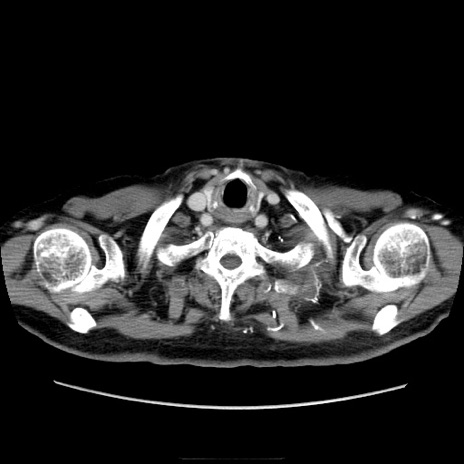

冠状断像

【症例】70歳代男性

【主訴】腹痛

【現病歴】肝硬変・肝細胞癌にてかかりつけの方。約9時間前に食後より腹痛出現。症状が徐々に増悪し、嘔吐出現したため来院。

【既往歴】肝硬変、肝細胞癌(RFA、TACE後)

【身体所見】意識清明、表情苦悶様、BT 36℃、BP 129/78mmHg、P 88bpm、SpO2 97%(RA)、右上腹部から心窩部にかけて圧痛あり、反跳痛なし、筋性防御あり。

【データ】WBC 5800、CRP 0.16